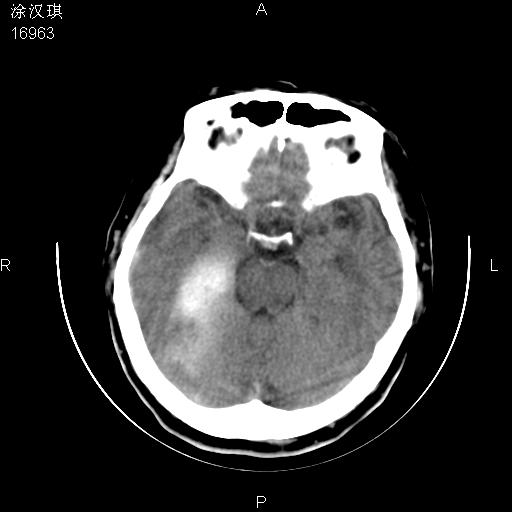

以下是引用chinazhouhua在2008-5-1 12:06:00的发言:[br]影像上来看,这是个典型的硬膜下血肿,包括右侧额颞部、大脑镰下、小脑幕下,而且在右侧额颞顶枕部、大脑镰下没看到高密度出血向脑沟内延伸,但是小脑幕下硬膜下有时候和蛛血不是很好鉴别,而且硬膜下很多时候伴有蛛血,往往在复查的时候出来,所以这种病人还是应该考虑硬膜下血肿伴有蛛血。

以下是引用zsl6918在2008-5-1 15:34:00的发言:[br]本病例主要表现为急性硬膜下血肿。

以下是引用深泽交通医院在2008-5-1 10:36:00的发言:[br]蛛网膜下腔出血

以下是引用形影不离在2008-5-1 11:32:00的发言:[br]支持 硬膜下血肿伴蛛网膜下腔出血,建议短期复查。